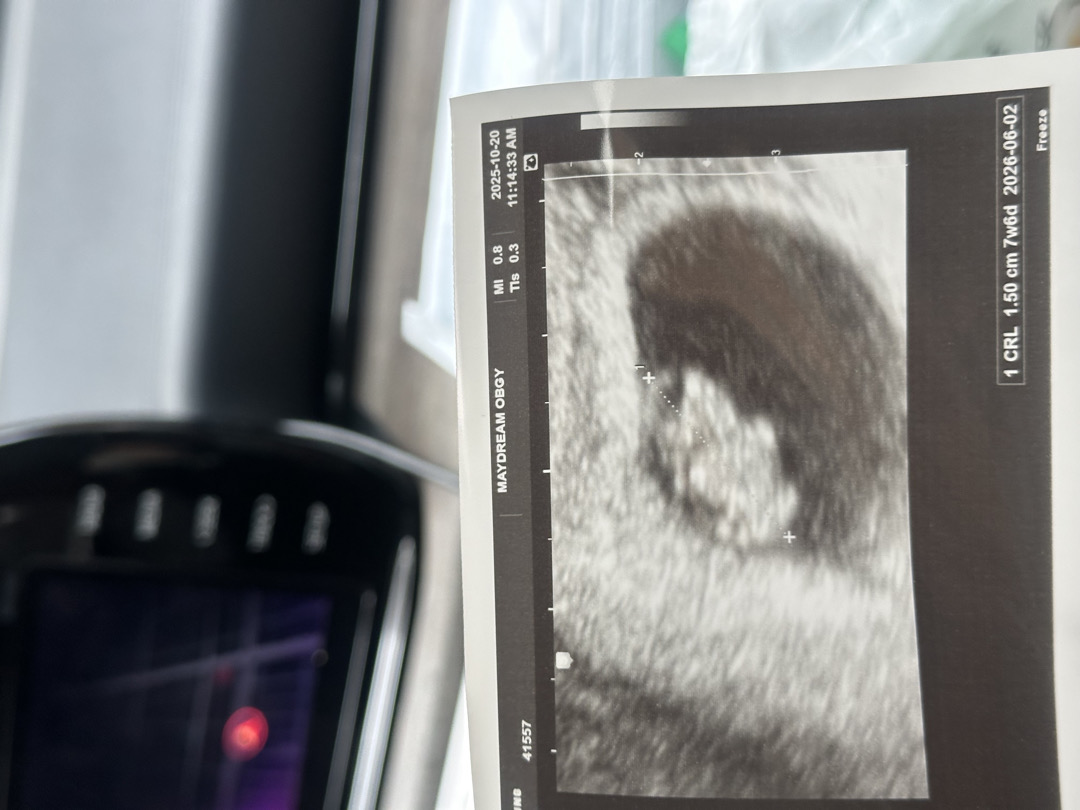

7주 차 6일 초음파 보고 왔어요👶🏻

1.5cm 163bpm 너무 신기하네요👶🏻🩷🩷🩷